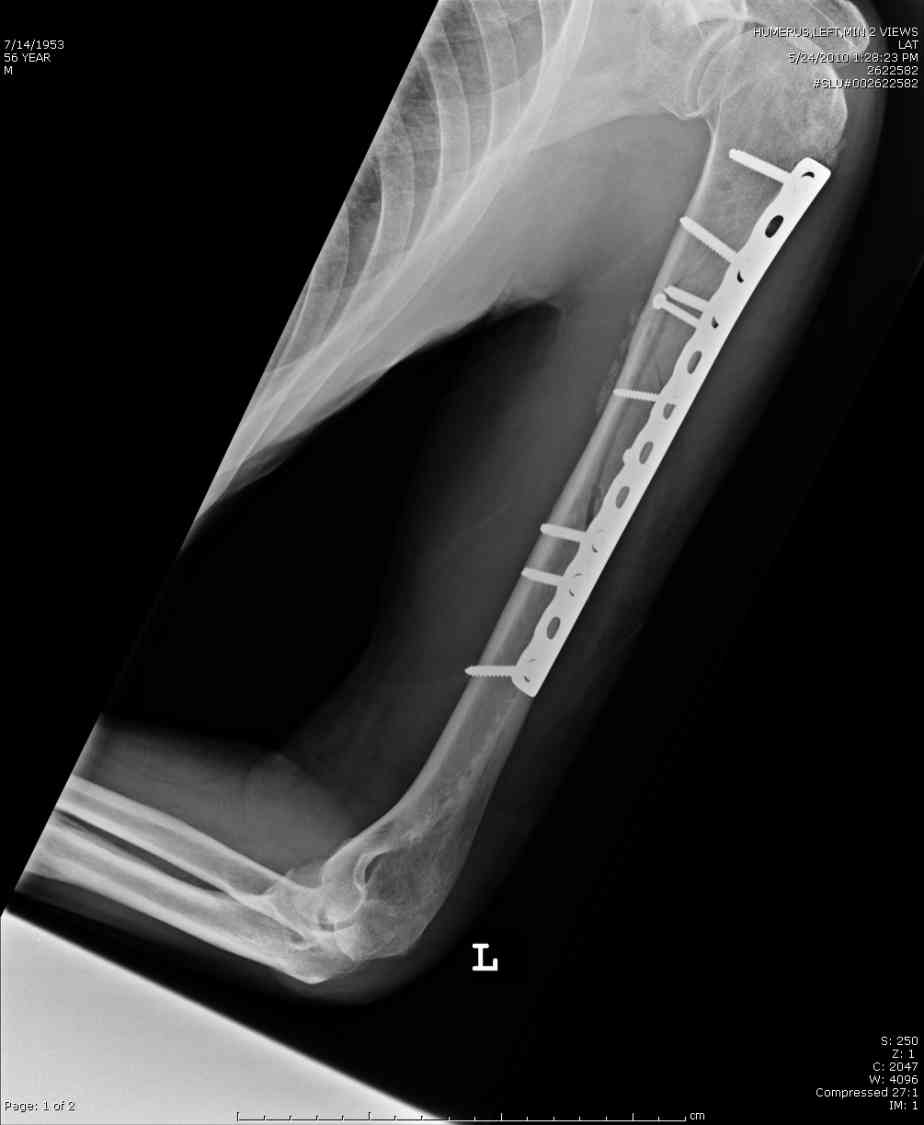

Александр А. 01 Июль 2010, 00:29

Добрый вечер!

Приложение как пример.

Спасибо.

Консервативно он уже лечился до этой операции в течение трёх с половиной месяцев.

А именно такой вариант операции выбран из экономических соображений.

вообще, торчашие в субакромиальное пространство шипы оставляют неизгладимое впечатление. Не думаю, что таким имплантом есть смысл гордиться